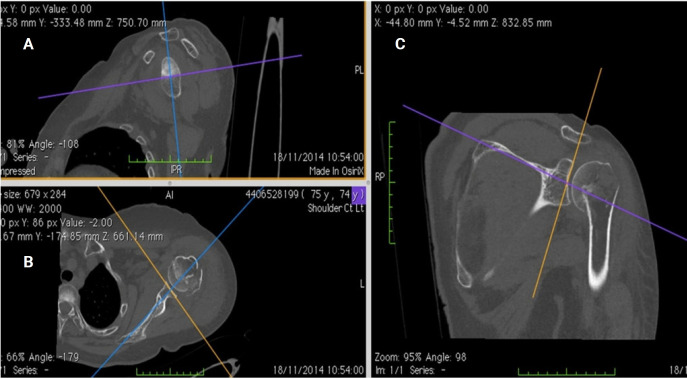

Methods: Shoulder CT scans for arthroplasty were analyzed retrospectively. Glenoid version was measured at the estimated glenoid midpoint using unformatted and formatted 2D-CT in the scapular plane. Measurements from 3D-CT reconstructions using the Corrected Friedman Method were used as the control. Inter- and intra-observer reliability was calculated as well as minimally detectable difference.

Results: Sixty-five CT scans were analyzed (mean age, 61.7 years). Mean glenoid version was -3.48° (standard deviation [SD], 8.7°) on unformatted 2D-CT, -3.27° (SD, 8.15°) on formatted 2D-CT, and -4.25° (SD, 7.92°) on 3D-CT. Although no significant difference in mean values was observed (analysis of variance, P=0.245), formatted 2D-CT measurements were within 6° of 3D-CT in 95.4% of cases versus 83.1% for unformatted 2D-CT (P=0.023). Directional error occurred in 27.7% of unformatted scans and 16.9% of formatted scans. Inter-observer reliability was highest for 3D-CT (intraclass correlation coefficient [ICC]=0.83; 95% CI, 0.74-0.89), and intra-observer agreement was strongest for 3D-CT (ICC=0.91; 95% CI, 0.86-0.94), followed by formatted 2D-CT (ICC=0.83; 95% CI, 0.73-0.89) and unformatted 2D-CT (ICC=0.77; 95% CI, 0.65-0.85).

Conclusions: 3D-CT reconstructions are widely considered the most accurate and reproducible method for glenoid version assessment, supported by multiple comparative imaging studies. Formatted 2D-CT provides a reliable alternative when 3D-CT is unavailable, significantly outperforming unformatted 2D-CT in both agreement with the 3D reference and intra- and inter-observer reliability. Level of evidence: IV.